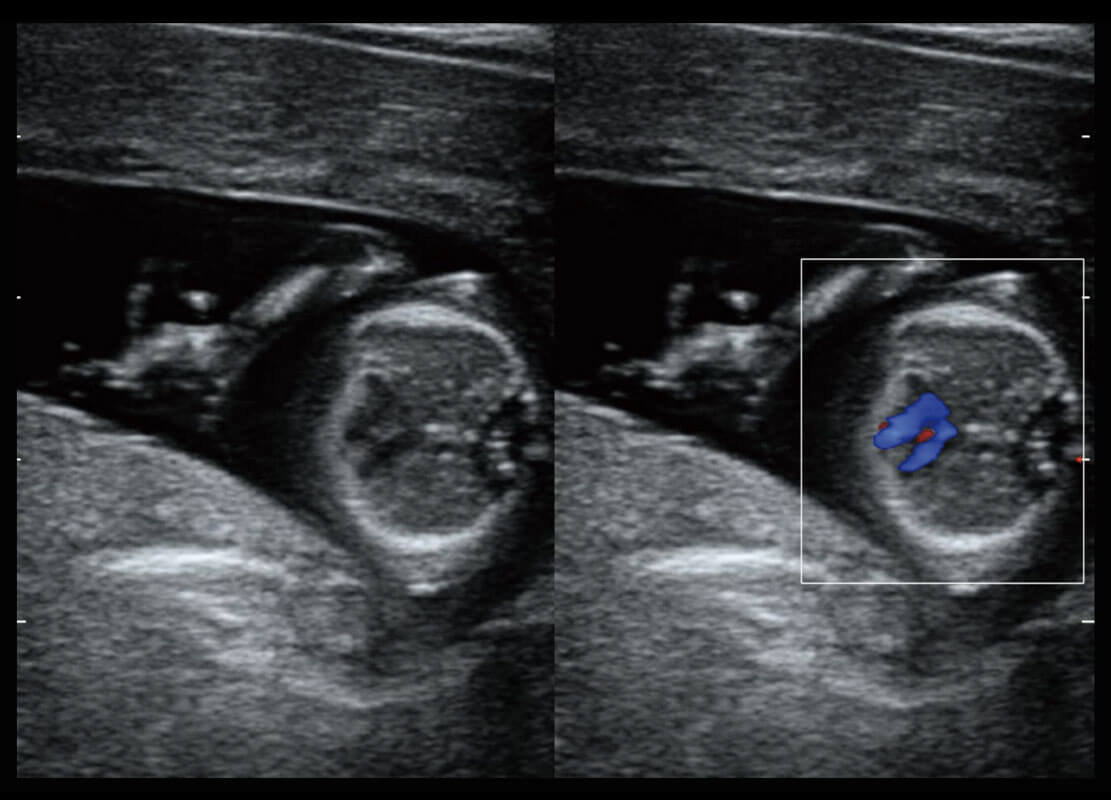

P60搭载宽频带线阵探头、宽景成像、弹性成像技术,为您提供乳腺应用方案。P60支持高频相控阵探头、线阵探头、腹部高频探头、腹部微凸探头等,丰富的探头群搭载敏感的彩色血流成像,适用于新生儿多种脏器检测要求,满足新生儿筛查需求。

新生儿肝血管癌

新生儿脊髓圆锥

新生儿心脏